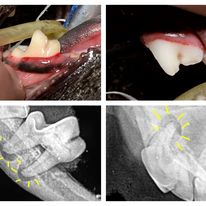

Within hours of eating plaque begins to form on teeth that can eventually mineralize into calculus or tartar. This tartar is the start of dental disease. It provides a good hiding place for bacteria and can irritate the gums leading to periodontal disease. Periodontal disease is when bacteria attack the tissues that hold teeth in place. They can even destroy the bone around the teeth creating pockets that become filled with pus. 85% of cats and dogs over 3 years of age have periodontal disease somewhere in their mouth. When the periodontal disease becomes severe owners will often report that their pets breath has become horribly smelly. Without treatment the animal will suffer with chronic pain, possibly get heart liver or kidney disease due to bacteria in the blood stream, and eventually lose teeth.

Once periodontal disease has started the only treatment to stop the disease process is a professional dental cleaning. This treatment can only be done under general anesthesia. A complete oral examination, which is an important part of a professional dental cleaning procedure, is not possible in an awake patient. The surfaces of the teeth facing the tongue cannot be examined, dental x-rays cannot be taken, and areas of disease and discomfort are likely to be missed. The most important part of the cleaning/scaling is the removal of bacteria and tartar underneath the gum line where the active disease process is going on. This can be painful and cannot be performed in an awake patient. A dental cleaning in an animal with periodontal disease without scaling under the gums does not improve oral health it just makes the teeth look cleaner in the short term and gives the owner a false sense of security.

As most pets that we perform dental cleanings on are older and have never had their teeth brushed they often require preanesthetic blood work, IV fluids, dental x-rays, and sadly extractions. Depending on the severity of the disease present the procedure can become quite costly. This is unfortunate when simply brushing once a day makes such a huge difference. It is important to start brushing at an early age and make it a fun and exciting event for your pet. Not all older pets will tolerate teeth brushing, some already have painful disease in their mouth and others won’t understand the fun and excitement no matter how much you try and convince them. For these pets there are special diets designed to brush their teeth while they eat.